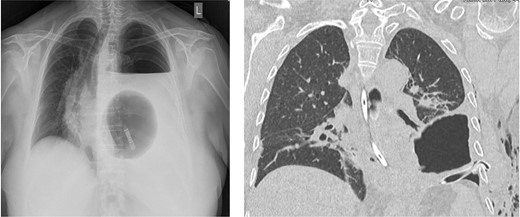

A 67-year-old female patient was admitted to the emergency department of our hospital with upper abdominal pain and vomiting. Previous medical history included a laparoscopic hiatal hernia repair in October 2018 due to a type III hiatal hernia and re-do surgery with mesh repair and a Toupet 270° posterior wrap due to a recurrence of the hiatus hernia with gastroesophageal reflux disease (GERD) in May 2019. Imaging studies revealed a new recurrence with total intra-thoracic stomach and compression of the left lower lung lobe (Fig. 1).

Chest/abdomen computed tomography showing a new recurrence with complete up-side-down stomach and compression of the left lower lung lobe.